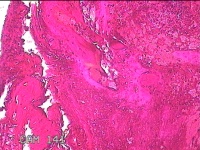

宫腔内容物

性别

女

年龄

28岁

临床诊断

不全流产?

一般病史

人流术后1月余,发现宫腔异常回声4天。

标本名称

大体所见

灰白暗红色不规则碎组织3x2.8x0.8cm一堆。

见胎盘绒毛。